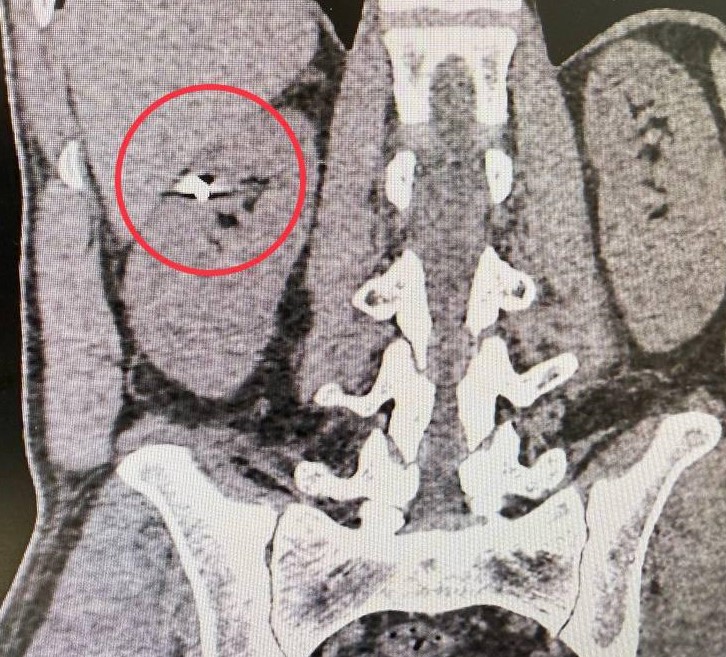

Около года назад 35-летний житель Подмосковья получил травму, в результате которой кусок металла размером 1 см. попал в брюшную полость, прошел через печень и попал в паренхиму почки — совокупность крошечных нефронов. Именно они фильтруют кровь и выводят ненужные вещества из организма.

— По данным компьютерной томографии мы зафиксировали осколок в верхней части правой почки. Печень была тесно припаяна к почке, и извлечение осколка могло привести к серьезному кровотечению и потере органа. Мы сделали резекцию почки, причем лапароскопическим методом, и извлекли осколок. Операция длилась около двух часов и прошла успешно. Главное у нас получилось сохранить орган, — подчеркнул Селим Везирханов заведующий урологическим отделением.